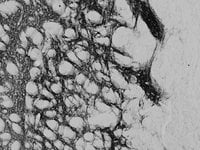

IHC (Immunohistochemistry)

((0. 02ug/ml) staining of PFA-perfused cryosection of Rat Striatum. HRP-staining with Ni-DAB after Biotin-SP-anti-goat amplification. Data obtained by Prof. Erik Hrabovszky, Inst, Exp, Med. , Budapest, Hungary.)